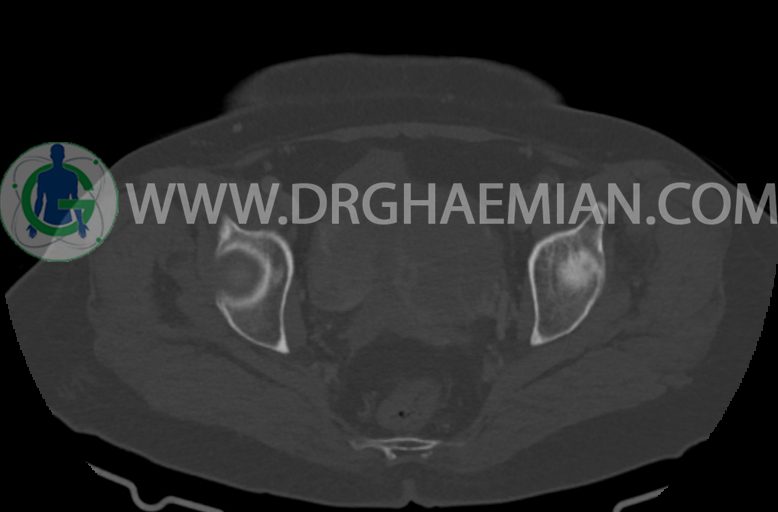

مایع آزاد در حفره شکم و لگن رویت نمی شود. ضایعه ای در مثانه مشهود نیست.

–ضایعه ی mass like هیپردنس- هتروژن به قطر 42mm در سمت راست لگن

–تغییرات DJD در L5/S1

مشهود است.